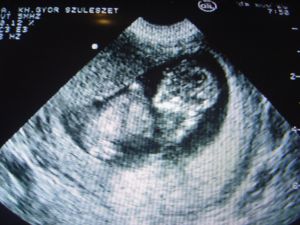

Köszi a babával minden rendben lesz. Persze az ember bizonytalan, mert itthon nincs kéznél egy UH - hogy gyorsan ránézhessek.